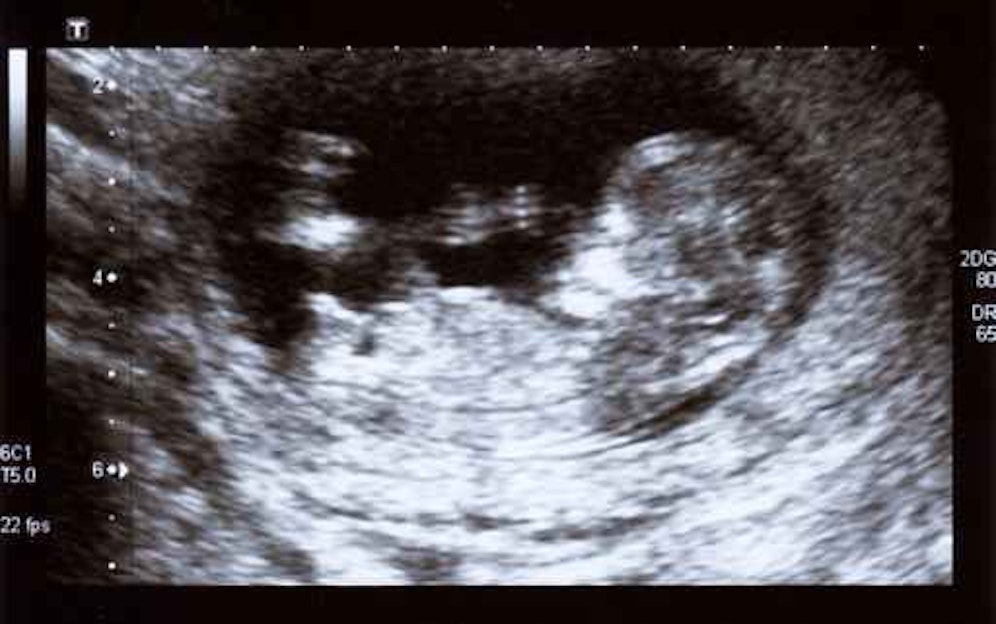

Eine Fallstudie der Universität von Miami zeigt, dass eine Covid-19-Infektion die Plazenta durchbrechen und Hirnschäden beim Fötus verursachen kann.

Zwei solcher Fälle wurden auf der Neugeborenen-Intensivstation des Holtz Children's Hospital bestätigt. Bei beiden Neugeborenen erkrankten die Mütter im zweiten Trimester an Covid-19. Beide Babys wurden bei der Geburt negativ auf Corona getestet, hatten aber eine "signifikant erhöhte" Anzahl der Covid-Antikörper im Blut. Das deutet darauf hin, dass die Antikörper entweder die Plazenta oder das Virus selbst passiert haben, was wiederum eine Immunantwort des Fötus auslöst.

Beide Kinder wurden mit kleinen Köpfen, Krampfanfällen und Entwicklungsverzögerungen geboren. Ein Kind starb nach 13 Monaten.